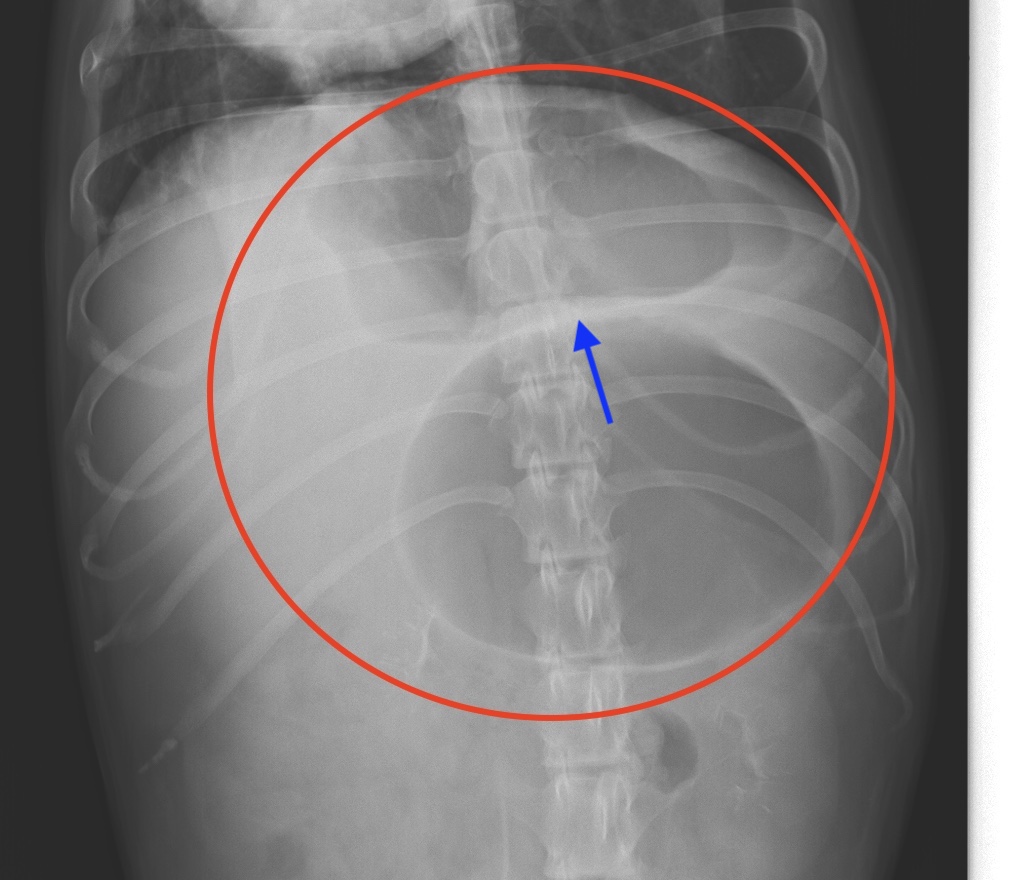

犬の胃拡張・胃捻転症候群は、胃が多量のガスで膨れ上がり(胃拡張)、胃がねじれること(胃捻転)によって発症する病気です。単純に胃拡張だけ起こしてねじれを生じないケースもありますが、圧倒的にねじれを起こすほうが多いです。

胃拡張・胃捻転症候群の病態を説明すると、まず、何らかの理由により急速に胃の中でガスが多量に発生して胃拡張が生じます。胃が大きく風船のように膨らむと、くるんと回転して強いねじれが生じ、食道への道が塞がれ、胃からの排出も障害され、さらに拡張が進みます。